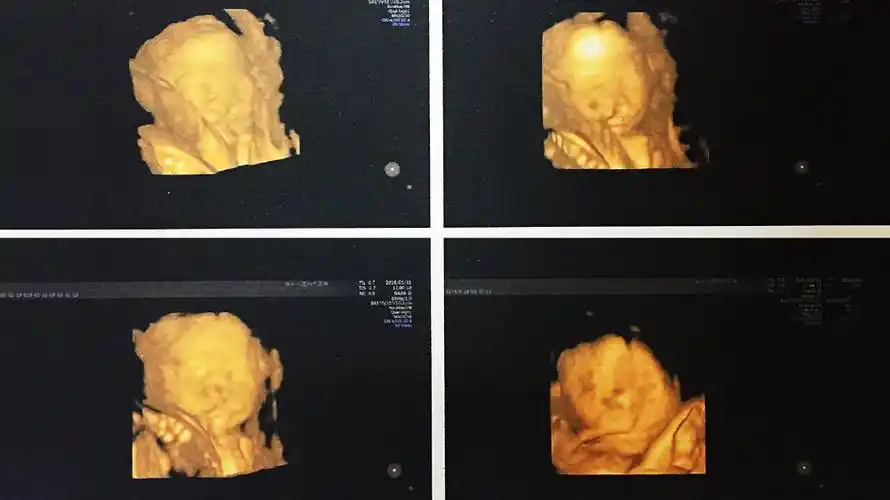

双胎宝妈21周做四维彩超筛查出一名胎儿为唇腭裂

双胎宝妈21周做四维彩超,筛查出一名胎儿为"唇腭裂"